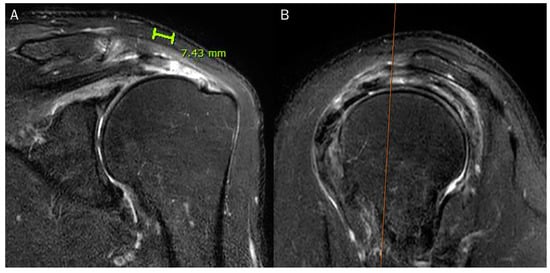

| 2 | retraction length of the articular and bursal layers |

| length of the intrasubstances cleavage | |

| length of the anteroposterior tear | |